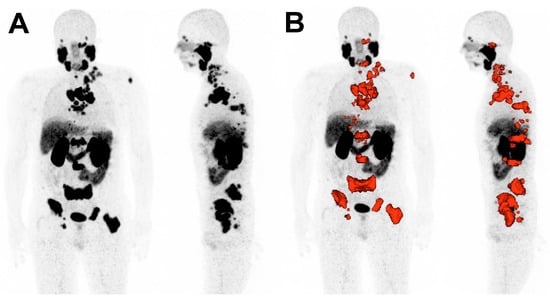

The imaging biomarkers to be analyzed included the maximum standardized uptake value of the tumor lesions (SUVmax), the mean standardized uptake value of all tumor lesions (SUVmean), the whole-body molecular tumor volume (MTV), and the whole-body total lesion PSMA (TLP), which is the analogue parameter to the established total lesion glycolysis (TLG) on [18F]FDG PET/CT [23,24]. TLP was defined as the summed products of volume and uptake (∑ Volume × SUVmean) of all lesions. MTV and TLP were calculated by a semi-automated tumor segmentation algorithm using Syngo.Via software (Enterprise VB 40B, Siemens, Erlangen, Germany). A standardized uptake of SUV ≥ 3 was used as a threshold for delineation of tumor lesions as described by Ferdinandus et al. [25]. Lesions that fell below a volume < 0.2 mL were excluded. Physiological uptake, e.g., in the bladder, spleen, liver or salivary glands, was manually excluded. Liver metastases were segmented by a threshold value of 1.5 × SUVmean of non-metastatic liver tissue. Figure 1 depicts exemplarily tumor segmentation using Syngo.Via software (VB 40B).

Figure 1. Representative example of tumor delineation using Syngo.Via software (VB 40B). (A): Maximum intensity projection (MIP) of [68Ga]Ga-PSMA-11 PET/CT. (B): Tumor tissue is delineated in red.